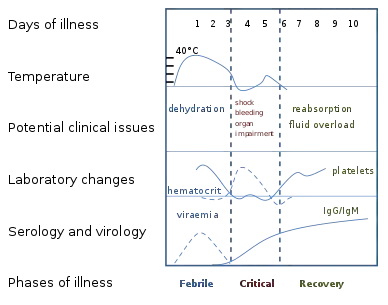

The characteristic symptoms of dengue are sudden-onset fever, headache (typically located behind the eyes), muscle and joint pains, and a rash. An alternative name for dengue, "breakbone fever", comes from the associated muscle and joint pains.[22][28] The course of infection is divided into three phases: febrile, critical, and recovery.[21]

The febrile phase involves high fever, potentially over 40 °C (104 °F), and is associated with generalized pain and a headache; this usually lasts two to seven days.[21][28] Nausea and vomiting may also occur.[27] A rash occurs in 50–80% of those with symptoms[28][29] in the first or second day of symptoms as flushed skin, or later in the course of illness (days 4–7), as a measles-like rash.[29][30] A rash described as "islands of white in a sea of red" has also been observed.[31] Some petechiae (small red spots that do not disappear when the skin is pressed, which are caused by broken capillaries) can appear at this point,[21] as may some mild bleeding from the mucous membranes of the mouth and nose.[17][28] The fever itself is classically biphasic or saddleback in nature, breaking and then returning for one or two days.[30][31]

In some people, the disease proceeds to a critical phase as fever resolves.[27] During this period, there is leakage of plasma from the blood vessels, typically lasting one to two days.[21] This may result in fluid accumulation in the chest and abdominal cavity as well as depletion of fluid from the circulation and decreased blood supply to vital organs.[21] There may also be organ dysfunction and severe bleeding, typically from the gastrointestinal tract.[17][21] Shock (dengue shock syndrome) and hemorrhage (dengue hemorrhagic fever) occur in less than 5% of all cases of dengue;[17] however, those who have previously been infected with other serotypes of dengue virus ("secondary infection") are at an increased risk.[17][32] This critical phase, while rare, occurs relatively more commonly in children and young adults.[27]

The recovery phase occurs next, with resorption of the leaked fluid into the bloodstream.[21] This usually lasts two to three days.[17] The improvement is often striking, and can be accompanied with severe itching and a slow heart rate.[17][21] Another rash may occur with either a maculopapular or a vasculitic appearance, which is followed by peeling of the skin.[27] During this stage, a fluid overload state may occur; if it affects the brain, it may cause a reduced level of consciousness or seizures.[17] A feeling of fatigue may last for weeks in adults.[27]